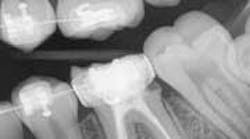

- Caries was clearly obvious around the fillings that were breaking down on Nos. 3 and 19. Its existence was definitely there prior to the placement of the orthodontic bands and wires. (It had only been four months!)

For the case presented here, thorough and detailed oral hygiene instructions were given by the hygienist, an electric toothbrush was suggested, and a four-month prophylactic rotation was recommended. Treatment entailed removing the bands and addressing the caries. Upon removal of the band on No. 19, there was very little tooth structure left. A new buildup with a stainless steel crown was placed. Due to the amount of leaking and lack of tooth structure, the patient’s mother was informed that the prognosis for the tooth was guarded.